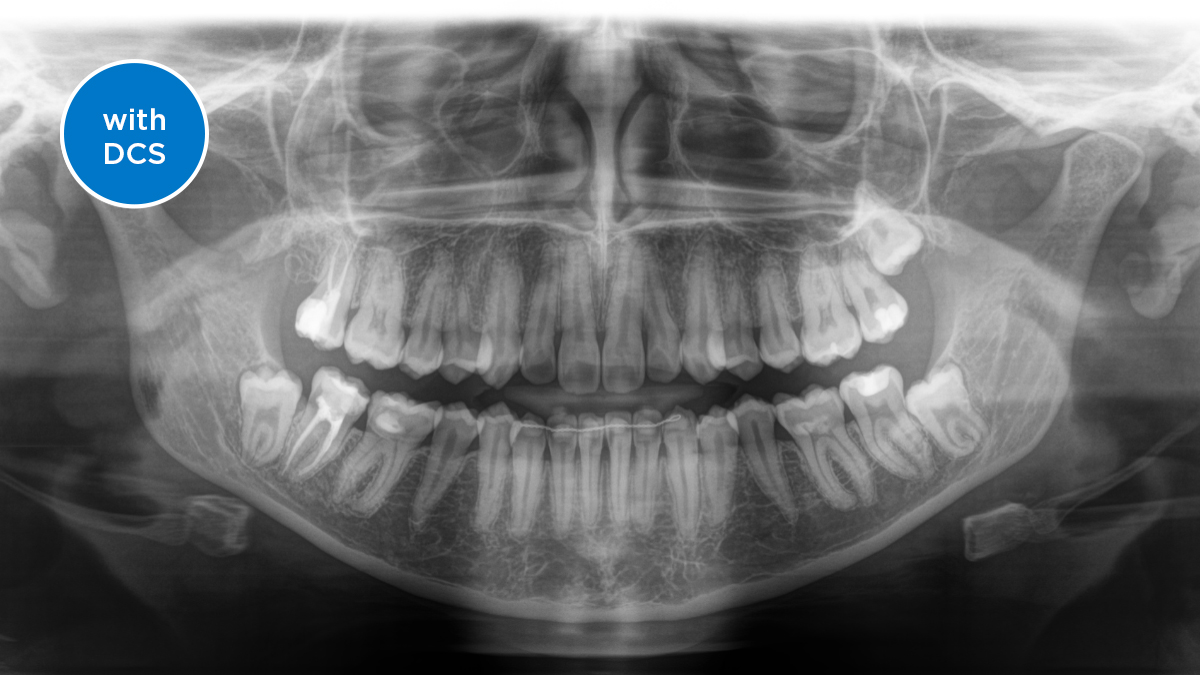

ダイレクト コンバージョン センサー(DCS) 画像診断を次のステージへ

ダイレクト コンバージョン センサー(DCS)によりパノラマ撮影品質を次のステージへ レントゲン画像は直接電気信号に変換されます。そのため、従来のシステムの場合のように、光信号への変換によるデータロスがなく、その結果、低い放射線量でも、非常に鮮明さと高いコントラストを備えた画像が得られます。適切な治療を支援するための正確な診断が可能になります。

サンプル画像は、DCSテクノロジーを使用していない場合と使用した場合のパノラマ画像です。矢印を使用してコントロールを画像上でドラッグすると、DCSセンサーが画質の質と診断の可能性に与える違いを確認できます。